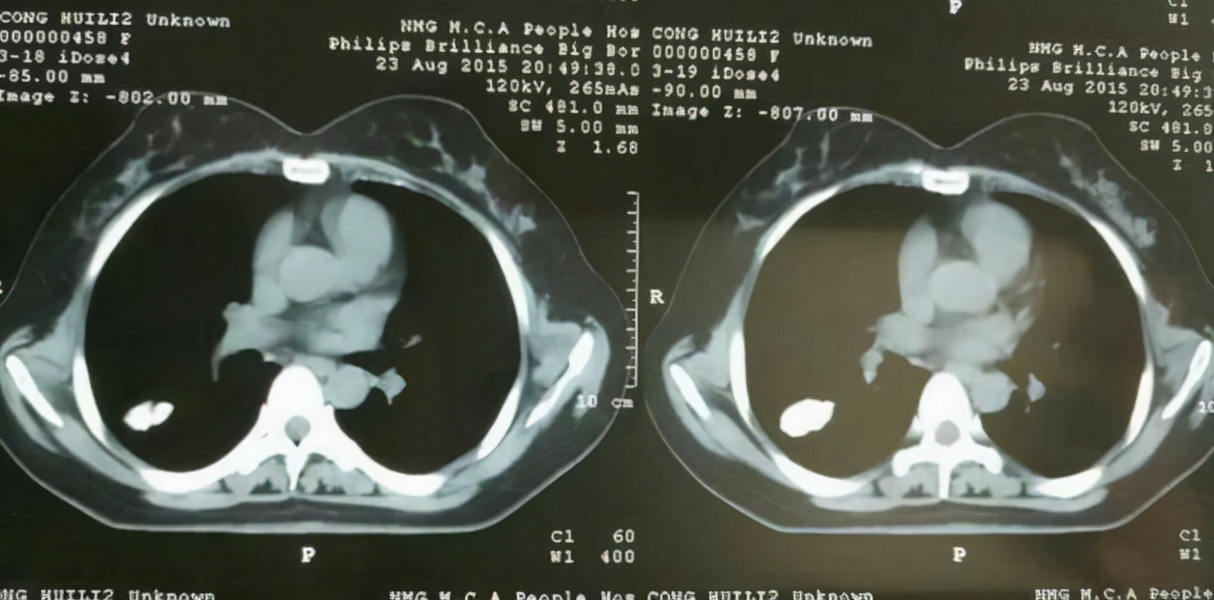

钙造化是指超声扫描时,在某个器官观察到的形态不规则,类似结石的钙质沉淀,检查图像显示 为白色亮斑,专业术语叫“强回声”。

钙化灶能够出现在身体的各个部位, 特别是在乳腺,甲状腺,子宫,肺部,前列腺等部位会引起钙化的疾病也特别多 ,良性和恶性疾病都有一定的可能。所以在体检时若是查出身体某些部位出现钙化,第一时间不要太过担心,可以找医生咨询一下,再根据临床症状结合 进一步检查作出准确的判断后,再针对性的进行治疗。